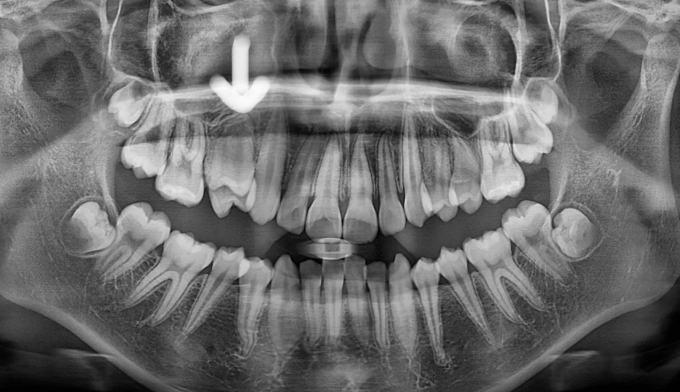

위 작은어금니가 겹쳐져서 맹출하였습니다.

유치를 발치할때 잘못된 순서로 발치하게 되는 경우 이런 경우가 발생할 수 있습니다.

유치 발치 후 영구치가 맹출할 공간을 확보해주어야 위와 같은 일이 생기지 않습니다.

공간이 부족하므로 먼저 양쪽으로 치아를 벌려 공간을 확보해준 후 겹쳐진 치아들을 배열해줍니다.

총 치료기간은 20개월입니다.